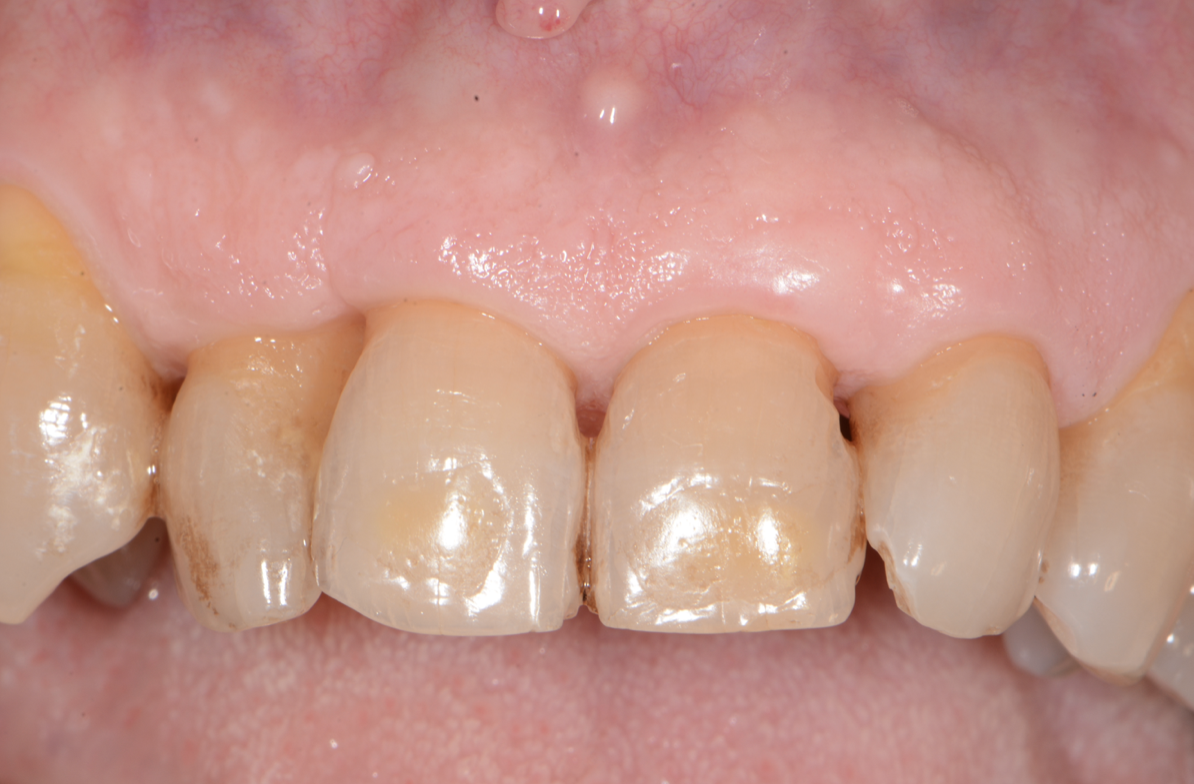

Epulide bilobata: caso clinico

È capitata la nostra attenzione una forma molto particolare di epulide, una doppia massa di altezza di 10 mm e larghezza di 12 su di una bocca con una igiene orale deficitaria con molta placca batterica ed imponenti depositi di tartaro.

L’esame microbiologico ha evidenziato una carica batterica di germi patogeni pari al 32% dove il complesso rosso e cioè di batteri ancor più patogeni, predominava al 91% .

Al paziente sono state fornite specifiche istruzioni di igiene orale, sottoposto a numerose sedute di pulizia professionale (detartrasi sopragengivale e scaling e root planing) e la massa è stata biopsata riscontrando una flogosi cronica, una fibrosi marcata e numerosi aspetti di iperplasia.

La chirurgia parodontale ha rimosso la massa esuberante ottenendo a distanza di 5 mesi un risultato ancora provvisorio ma incoraggiante.